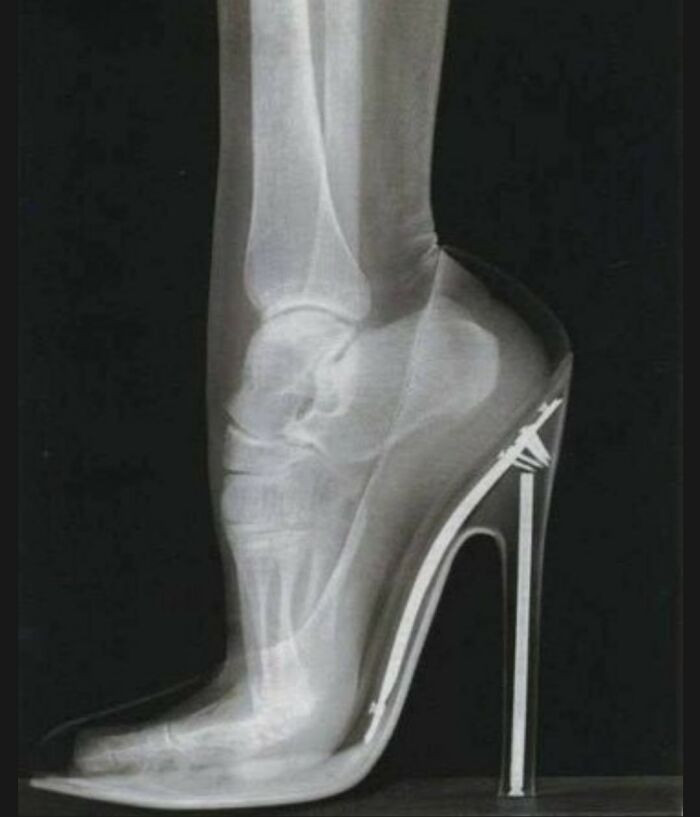

This X-ray shows the position of a foot when wearing a high-heeled shoe.

High heels may enhance a woman's beauty, but human biology teaches us that the body is not adapted to this accessory. Therefore, overusing high heels can cause severe problems due to the improper biomechanical stress placed on the entire body.

Wearing high heels forces the foot to be on its toes for extended periods. This causes the muscles to adapt to this position with a shortened length, and in fact, muscle shortening of the triceps surae (gastrocnemius and soleus) and plantar muscles has been demonstrated as a result of this posture. In the long run, this can lead to pain in the back of the knee.